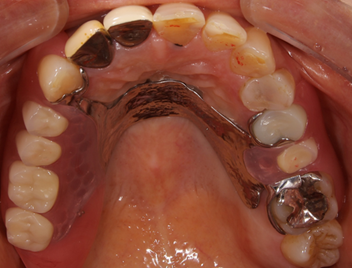

欠損部が左右に跨るようにあり、欠損範囲も広いため左右別々の義歯は噛み心地と適合性が落ちるため、既存の義歯と同じように左右一体型の義歯を採用しました。ただ今までと同じ設計では話づらさが改善しないため今回は上顎の真ん中に薄い金属を通すことで違和感を極限まで減らす自費義歯を作成していくこととしました。

義歯は上顎の真ん中に薄い金属を通すことで話ずらさを改善しました。金属をたくさん使用していますが歯に引っかかる針金は歯茎の形をしているため見た目は義歯を装着しているようには見えません。適合性もばっちりとれています。